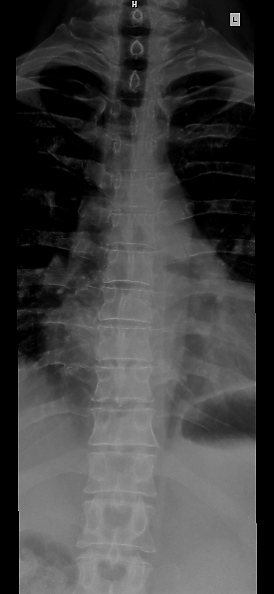

Позвоно́чный столб, или позвоно́чник (лат. columna vertebralis) — основная часть осевого скелета человека. Состоит из 32—33 позвонков, последовательно соединённых друг с другом в вертикальном положении[1][2]. Позвонки разделяют на отдельные типы: шейные, грудные, поясничные, крестцовые (срастаются в крестец) и копчиковые.

Различают 5 отделов позвоночника:

- Шейный отдел (7 позвонков, C1—C7);

- Грудной отдел (12 позвонков, Th1—Th12);

- Поясничный отдел (5 позвонков, L1—L5);

- Крестцовый отдел (5 позвонков);

- Копчиковый отдел (3-4 позвонков)[2], иногда до 5).